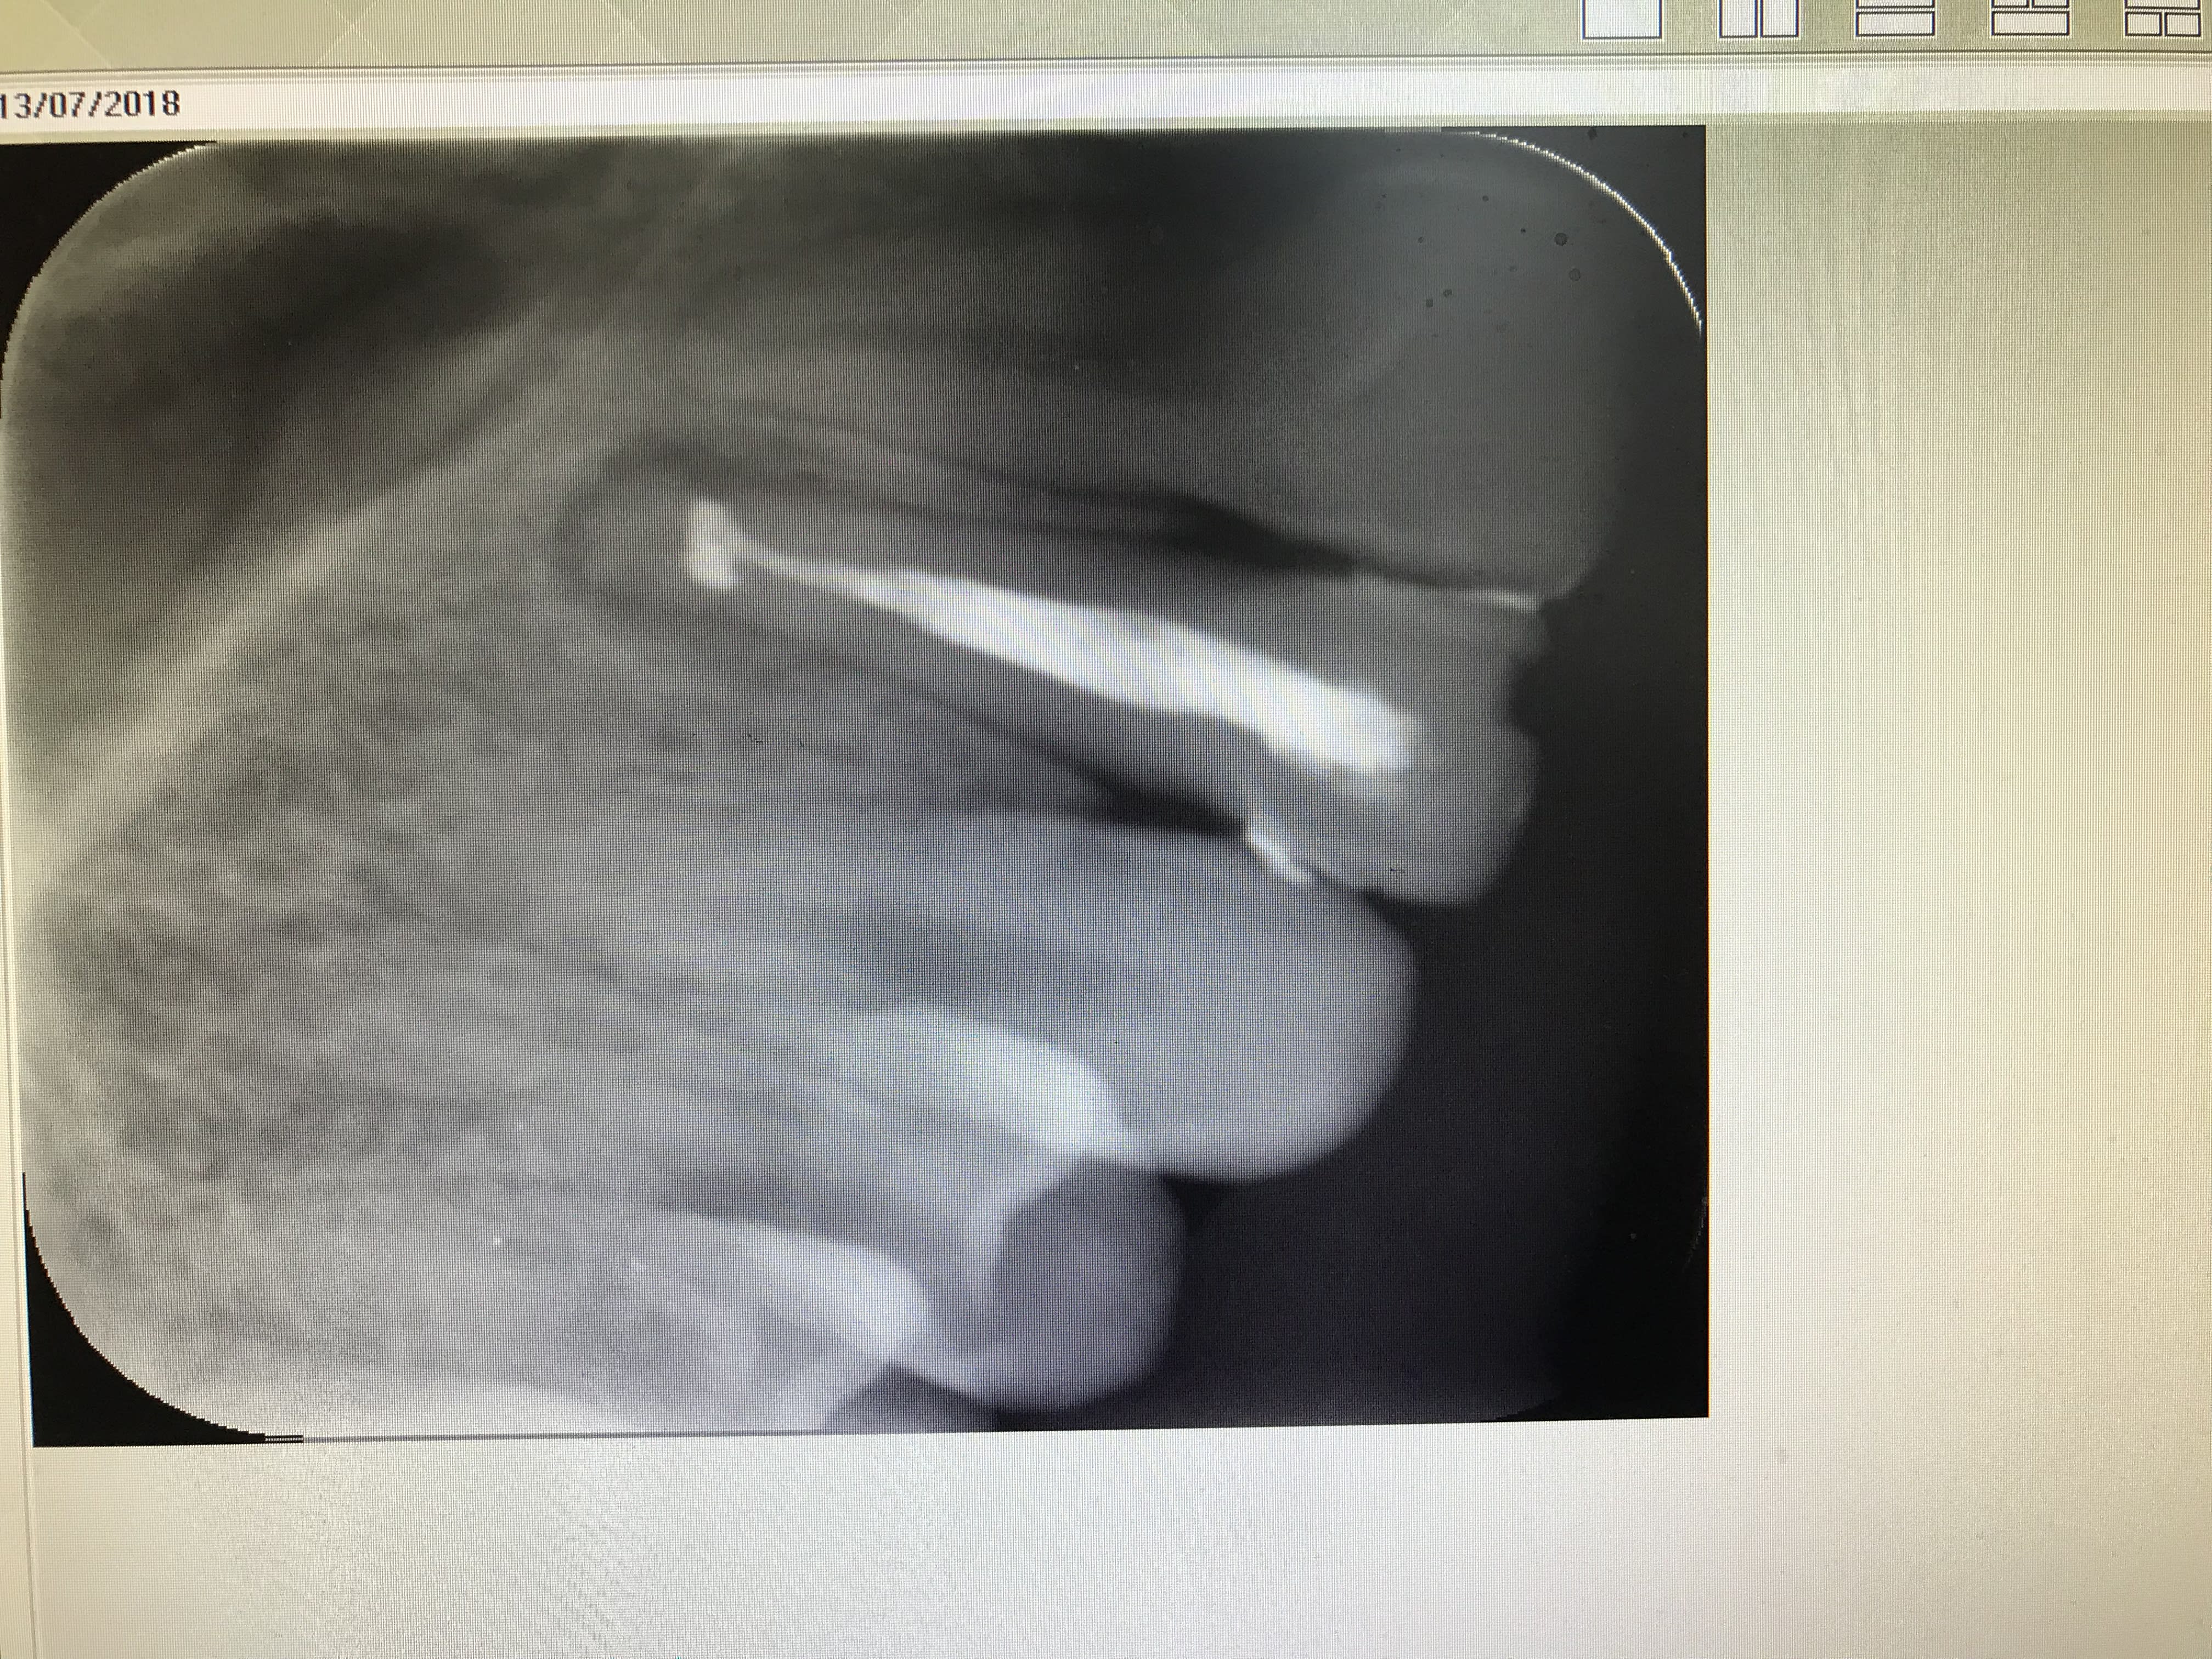

Et bien vous savez que certains lisent dans le marc de café. Moi je fais pareil avec les cônes de gutta . :))))

Regardez les endos d’aujoud’hui :

- la gutta part à l’horizontal ce qui nous indique que la France va gagner ...

- d’après le nombre d’endos et de cônes de gutta mis dans la même séance. Il n’ y aura pas 1 ni 2ni 3 .... mais bien 8 buts . Épatant non ?

Pourquoi tu t'arrêtes aux 4 chez ce patient qui apparemment a l'air d'avoir une bonne mutuelle ? On aurait pu les écraser un peu plus les croates et rentrer dans l'histoire. -))))